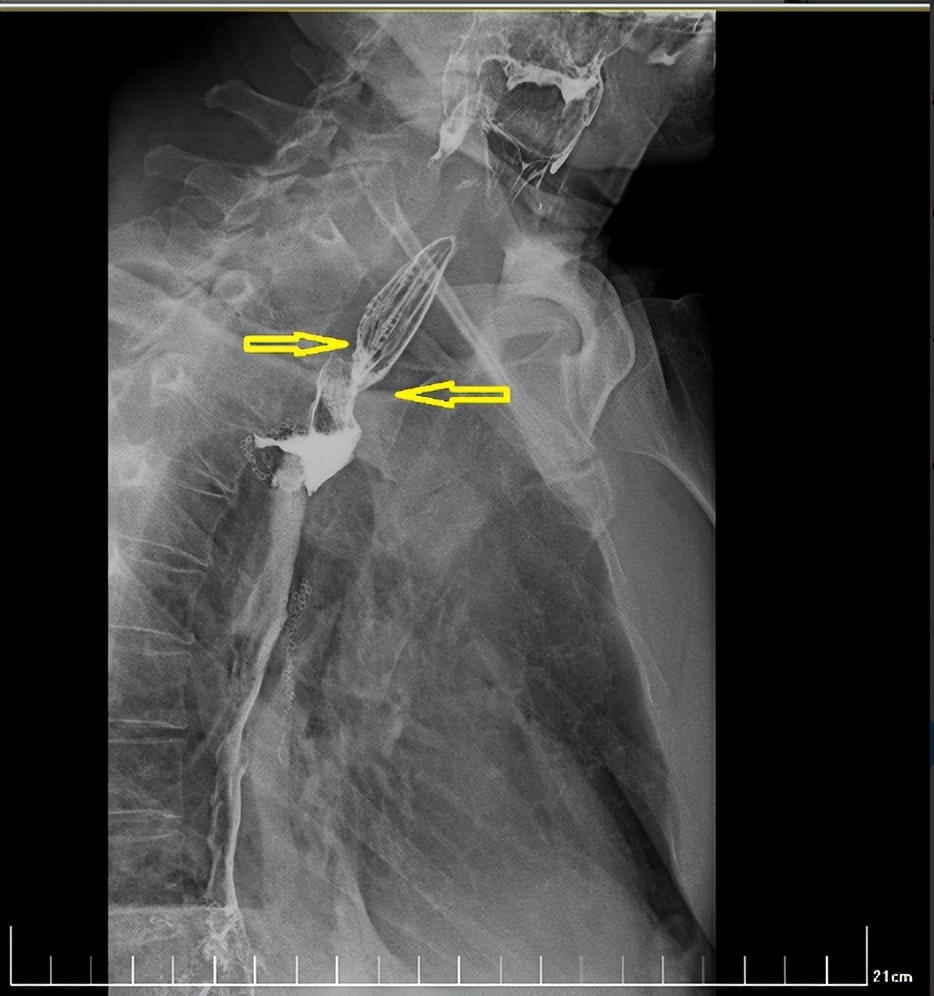

经过一个周期的放疗,李先生明显感受好多了,可以正常吃饭喝水。食管钡餐造影显示,食管吻合口区肿块明显缩小,食管狭窄减轻。

治疗后